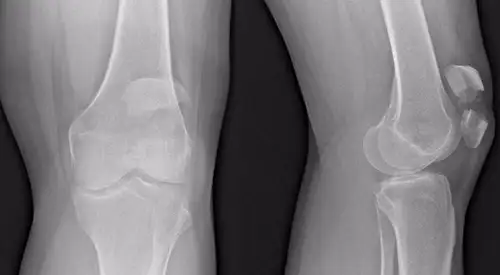

Las radiografías ayudarán a identificar la fractura de rótula.

En ocasiones se requiere la solicitud de pruebas complementarias (resonancia o TAC) para visualizar el estado del cartílago u observar con más detalle la fractura.